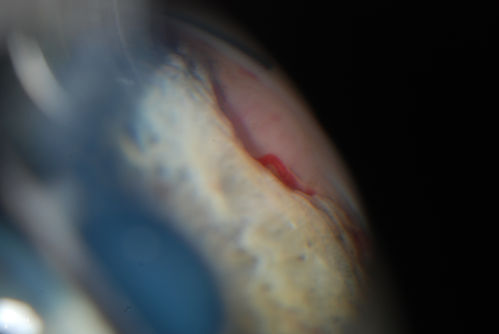

Gonioscopy, Mass in the Angle of Anterior Chamber

Slit Lamp and goinoscopy photos show a mass at 7-o'clock i the right eye. The mass extends beneath the iris behind the lens.